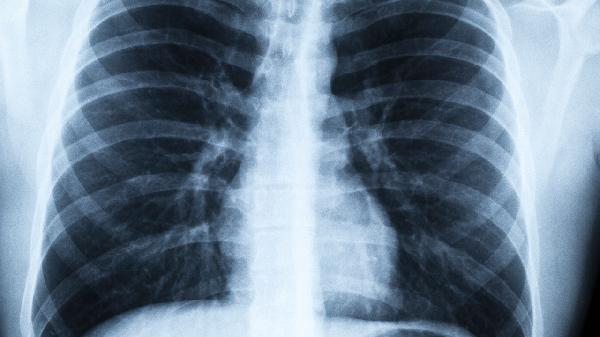

胸痛多呈针刺样,深呼吸时加重,与胸膜受累有关。肺部听诊可闻及湿啰音,严重时出现呼吸急促和口唇发绀。症状明显者需进行胸部影像学检查评估肺实质病变程度。